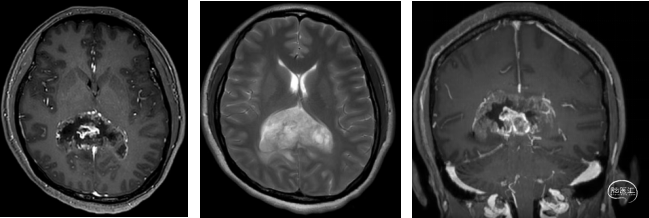

术前MRI

临床症状进行性加重,短期内出现头痛症状,影像学提示胼胝体压部占位,肿瘤紧邻三脑室顶后部、中脑顶盖、中脑导水管、四叠体池/脑深部引流静脉受压明显,占位效应重。

本例患者影像学上表现为累及胼胝体压部的典型的蝴蝶状胶质瘤,病变累及双侧半球,非对称分布。手术均用右侧顶枕叶造瘘+左侧纵裂入路,术中先后探查和分块切除大脑镰后部两侧的病变。大脑镰后部毗邻大脑深部静脉系统,需要尽可能避免损伤Galen静脉或下矢状窦等重要结构,左侧纵裂入路可能有利于实现更好的功能保护。位于胼胝体不同部位的蝴蝶状肿瘤,由于解剖基础和功能保护的需求,采取不同的入路,从而在尽可能保护脑功能的前提下安全切除病变。

蝴蝶状胶质瘤(Butterfly Glioblastoma,bGBM)是胼胝体胶质瘤(胶质母细胞瘤)和胼胝体周围脑胶质瘤(胶质母细胞瘤)的总称,一种指肿瘤原发于胼胝体内,肿瘤局限于胼胝体内或者肿瘤大部分位于胼胝体内,有部分瘤体向一侧或两侧大脑侵犯,病变呈“蝴蝶状”;另一种是指胼胝体附近的脑胶质瘤侵犯胼胝体,肿瘤大部分位于一侧大脑半球深部向中线部位生长,影像学表现为“半个蝴蝶状”[1]。

bGBM最常见的部位是额叶(64.1%)和顶叶(15.4%)。bGBM侵袭胼胝体最常见的部位是在膝部(48.7%)和压部(28.2%)。bGBM最常见的症状包括头痛、认知能力下降,包括意识混乱和记忆丧失,以及癫痫发作。后期可出现神经功能缺损及颅内高压症的表现。影像学诊断基本同胶质瘤,特征即肿瘤存在于胼胝体两侧,突入脑室及脑实质内[2]。